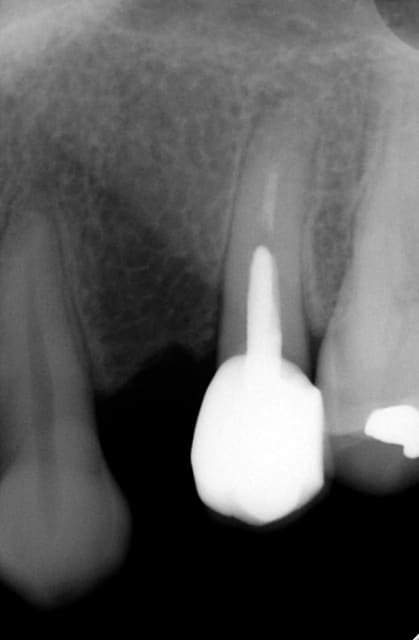

Oui,c´est un Prep cap zircone , que je cémente juste après l´implantation immédiate pour mieux former la gencive. Les implants monoblocs ont étés implantés entre 40 et 60 Ncm . Les photos 6 et 8 on voit les prep cap juste après l´implantation immédiate ce sont des sortes de "couronnes" pré fabriquées.

Oui , tu as raison pour la 45, en fait quand j´ai enlevé la 45 j´ai choisi l´axe comme ca ( dans l´os dur et en bon santé) parce que c´etait ici que je pouvais avoir la stabilité ( pour cet implant à 50 Ncm.

Voilà une patiente que je revois à deux ans apres la pose d'un monobloc Classic line 3,5/12mm et prep cap zircone 12 degres 2/2 en 24.

Radios 1,2,3 photo 1= jour de la pose de l'implant.

radio 4 photo 2 et 3= 8 semaines post pose de l'implant, ceramiques scéllées.

Radio 6, photo 4 et 5 controle à 24 mois.

Deux ans plus tard, la gencive a recouvert la zircone et on observe à la radio un gain osseux au niveau des micros spires.